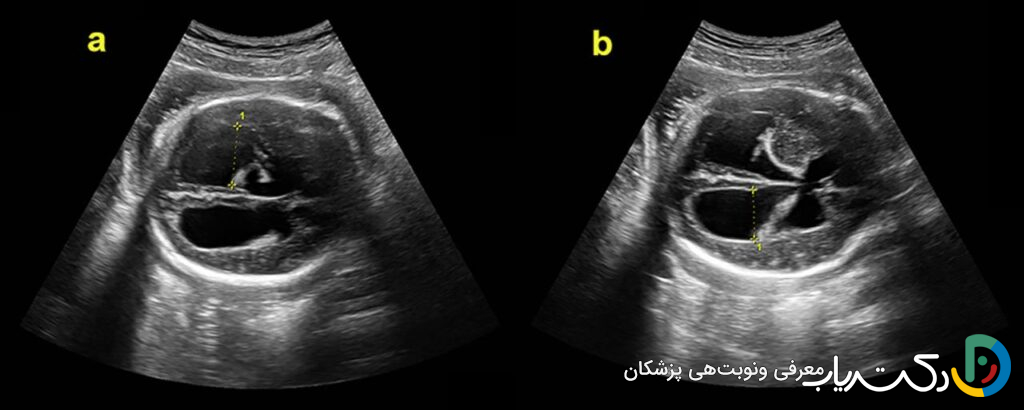

معیارهای تشخیصی در سونوگرافی: اعداد چه میگویند؟

متخصصان برای تشخیص و طبقهبندی شدت بزرگی بطنها، عرض دهلیز بطنهای جانبی را اندازهگیری میکنند. این بخش از بطنها به راحتی قابل مشاهده و اندازهگیری است و اندازه آن در نیمه دوم بارداری تقریباً ثابت باقی میماند.

- وضعیت نرمال: اندازه بطن کمتر از ۱۰ میلیمتر طبیعی تلقی میشود.

- ونتیکولومگالی خفیف : اندازه بین ۱۰ تا ۱۵ میلیمتر. این وضعیت همیشه به معنای هیدروسفالی فعال نیست، اما یک یافته مهم است که نیازمند بررسیهای دقیقتر و پیگیریهای مکرر است.

- هیدروسفالی آشکار یا شدید : اندازه بزرگتر از ۱۵ میلیمتر به وضوح نشاندهنده هیدروسفالی است و معمولاً با پیشآگهی جدیتری همراه است.